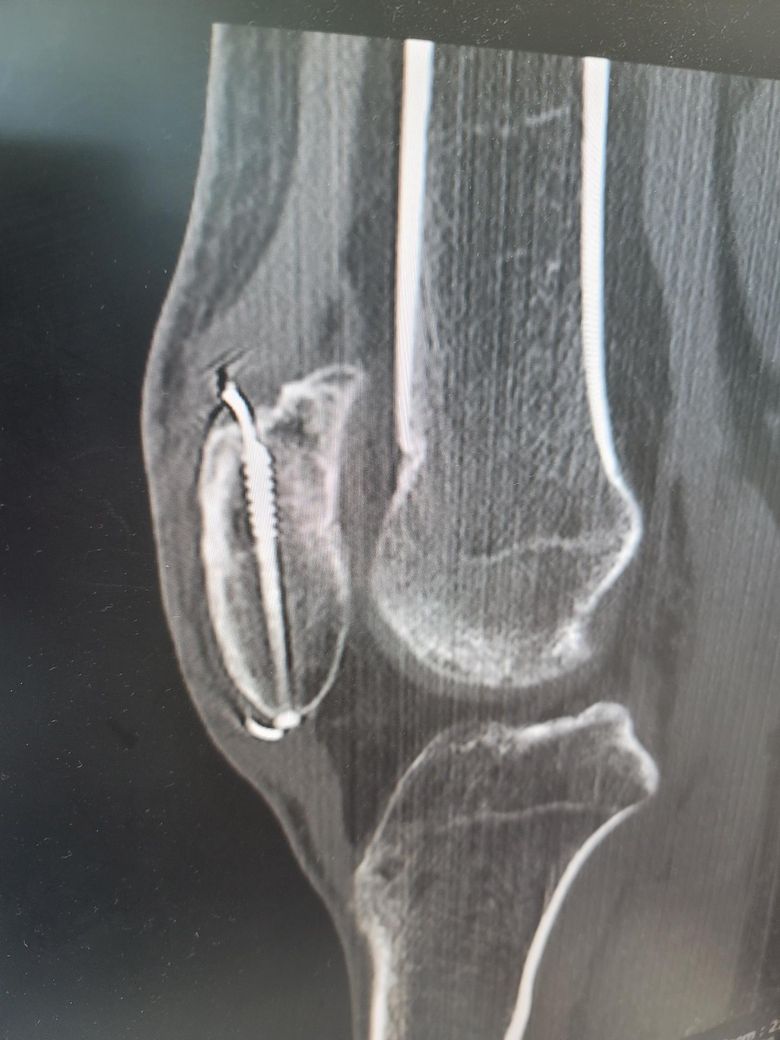

슬개골골절 수술후 5개월차입니다.

슬개골수술후 5개월차 ct입니다 분쇄골절 7조각이여도 엑스레이상 잘붙은즐알았는데 ct를찍어봤더니 양쪽 끝부분이 덜붙었더라구요 혹시 안붙으면 재수술하거나 뼈이식을 다시해야되나요? 걷거나 큰 통증은없는데

안붙을까봐 걱정입니다